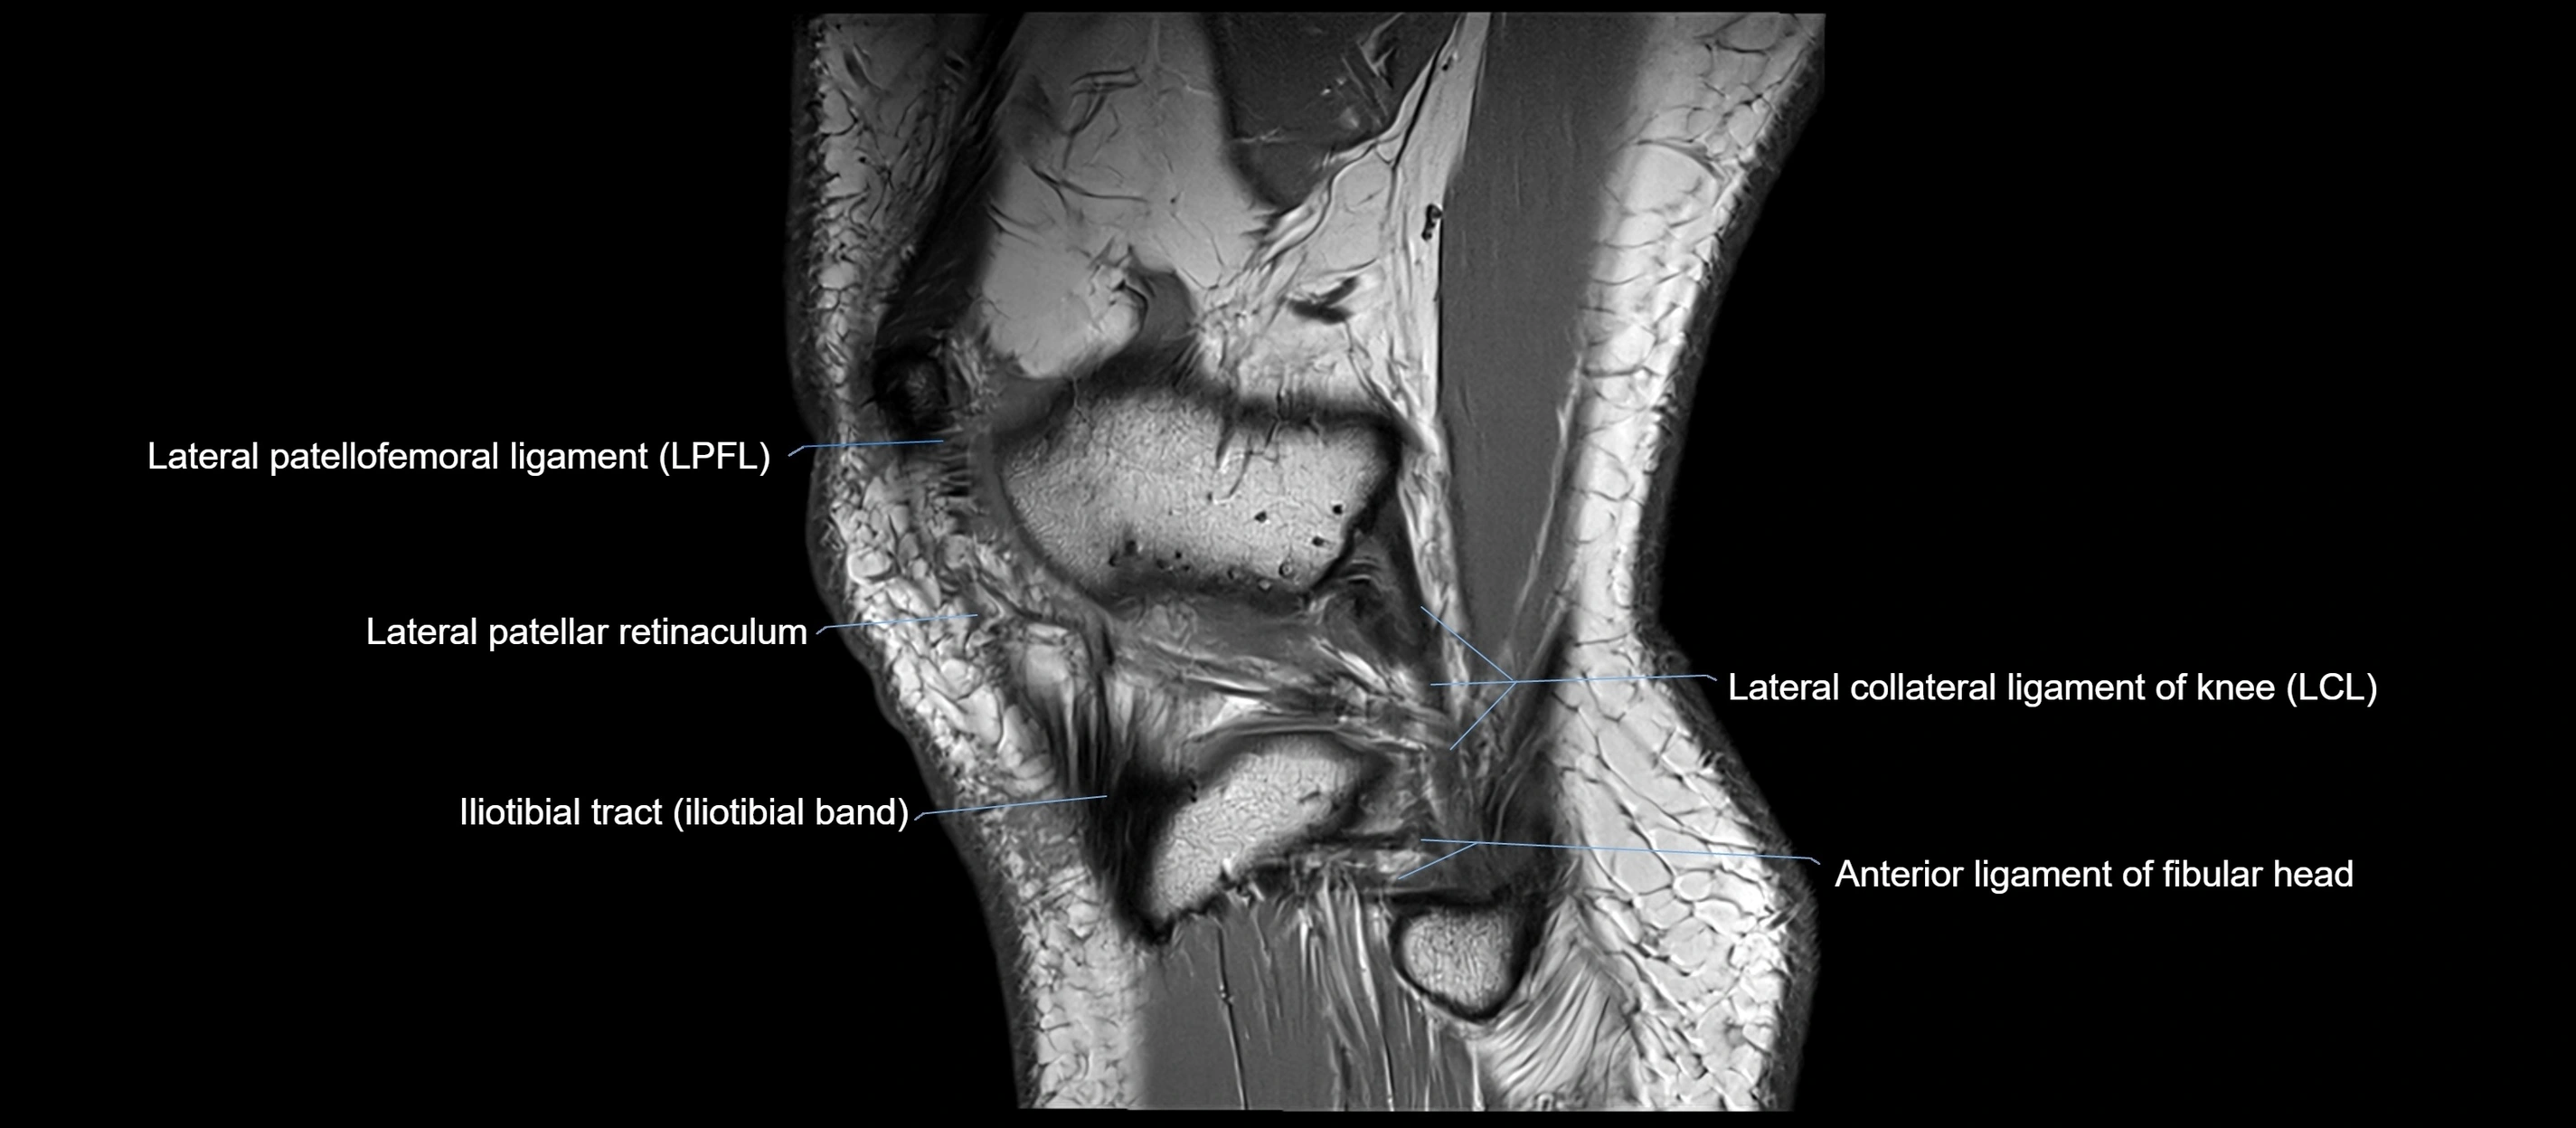

MRI images

image